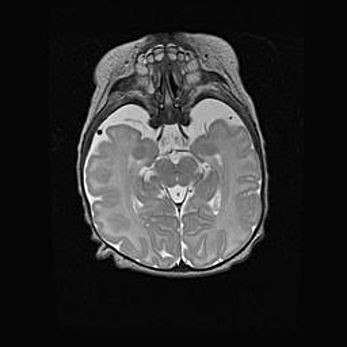

Подострая гематома правой гемисферы мозжечка.

Наружная гидроцефалия.

Возраст: 15 дней

Вес: 3100 г

Пол: женский

Окружность головы: 37 см

Срок гестации: 35-36 недель

При открытой наружной форме гидроцефалии у новорожденных расширяются и переполняются субарахноидные пространства.

Кровоизлияния в мозжечок имеют две клинико-анатомические формы: полушарные гематомы и кровоизлияния в червь.

К появлению этой патологии может привести: повреждения головного мозга, возникающие в результате асфиксии и гипоксии плода при беременности, или травмы во время родов. Редко гематома мозжечка может быть результатом первичной коагулопатии и сосудистой мальформации, диссеминированном внутрисосудистом свертывании, изоиммунной тромбоцитопении.